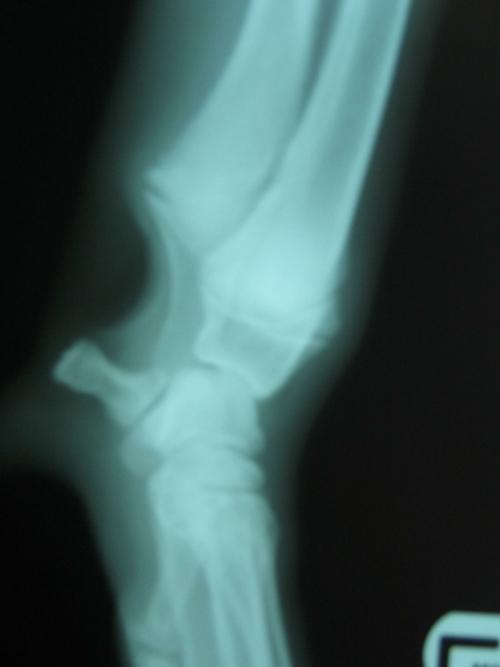

Radiologie :

Une salle spécifiquement dédiée à la radiologie et conforme aux normes actuelles en matière de radioprotection est aménagée dans la clinique. Le Dr Blanckaert est responsable de la radioprotection au sein de l'établissement.

Nous disposons sur place de deux appareils de radiologie :

- un appareil de radiologie numérique polyvalent haute Fréquence qui, grâce à un capteur plan et à une système informatique, permet d’obtenir des clichés radiologiques de haute qualité que nous nous chargeons d'archiver dans le dossier de votre animal ou de vous transmettre par voie informatique.

- un appareil de radiologie dentaire numérique (radiographie endobuccale) qui, relié à notre réseau informatique, nous permet de réaliser des bilans dentaires et des radiographies, de qualité et de définition exceptionnelles, des structures osseuses de la bouche ainsi que des parties les plus fines (extrémités des Nouveaux Animaux de Compagnie par exemple).